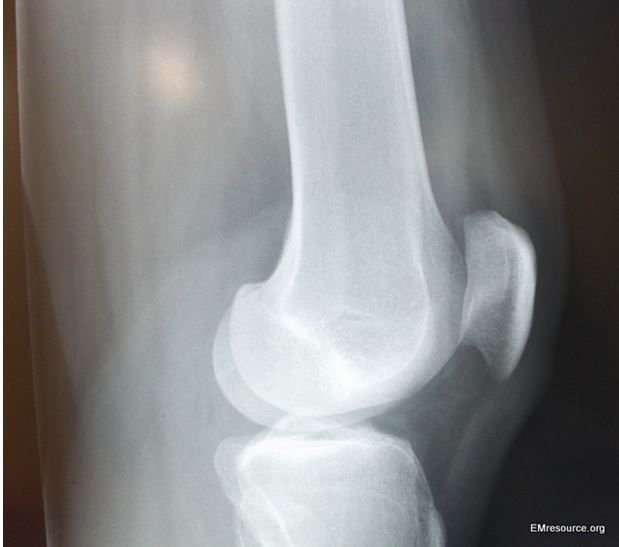

While demonstrating his retro dance moves, a 31-year-old injures his knee doing “the Twist.” Now he can barely walk. Would you order an x-ray?

You let your judgment trump the imaging criteria and order a knee x-ray film; results are shown at right in Figure 1.

If so, what finding(s) is/are demonstrated?